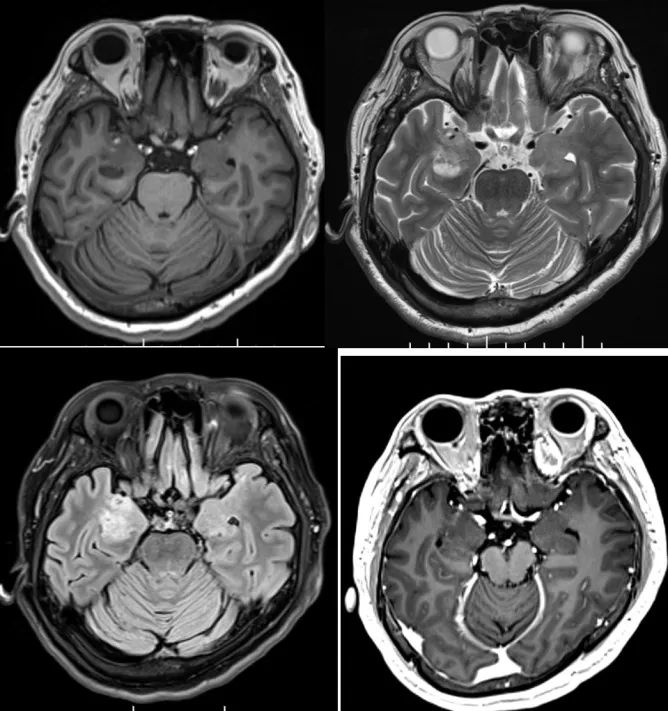

答案:枫糖尿病。枫糖尿病是由α-酮酸脱氢酶多酶复合体功能缺陷引起的常染色体隐性遗传病。婴儿起病的白质脑病要想到枫糖尿病。影像上要注意和Leigh综合征鉴别。Leigh综合征多在10岁以前发病,以婴幼儿多见;神经系统的主要表现为抽搐、卒中发作、眼外肌麻痹、痴呆、共济失调、视神经病变等。Leigh多为双侧对称性分布,病变形态不规则,大小不等,呈斑块状;病变主要累及双侧壳核及导水管周围灰质,也可累及丘脑(尤其是背内侧核)、小脑齿状核、脑干、脑白质和皮质均可受累;MRI呈长T1、长T2信号,T2-FLAIR和DWI像病变信号多不均匀。枫糖尿病特点为弥漫性的脑白质水肿,遍及大脑和小脑半球的TW2I上的高信号,尤其在基底节及脑干区。典型表现为侧脑室旁、基底节区、脑干、小脑T2WI及DWI上的高信号影,DWI显示的更加敏感;MRS在0.9ppm处可发现一个相对特异性的宽峰;同时可见NAA峰的下降及Lac峰的升高。